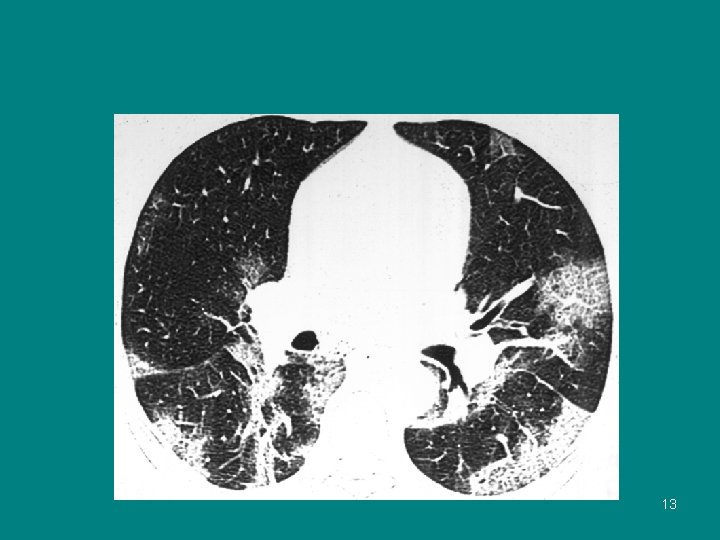

CT Thorax 13